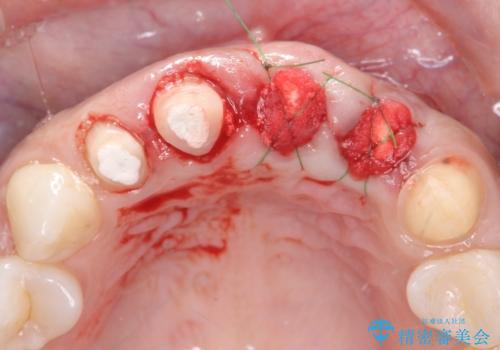

一見して問題ないように見える左側の2前歯は、セラミックを除去してみると亀裂や虫歯の再発が見られました。

抜歯時に可及的に歯肉のボリュームを保つよう骨充填材とコラーゲン製剤による填塞を行い審美的かつ機能的なブリッジとなるよう治療を進めます。